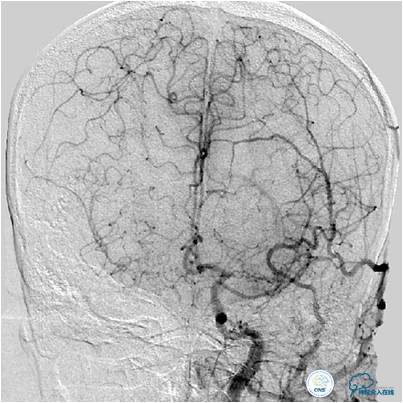

患者入院后,完善颅内CTA(图1)及血管造影(图2~3)检查,发现右侧颈内动脉颅内段闭塞,右侧大脑前动脉依靠左侧颈内动脉系统通过前交通动脉供血,右侧大脑中动脉供血区则依赖于右侧大脑前动脉(ACA)软脑膜代偿供血,左侧大脑中动脉闭塞,依靠一少见血管代偿供血,该血管起自左侧大脑前动脉A2段起始部,代偿供应左侧大脑中动脉供血区。由于该患者灌注CT(图4)未见明显低灌注区,遂给予患者抗血小板、降脂及控制危险因素治疗出院。出院后电话随访未再出现过上述症状。

图3A:左侧颈总动脉造影动脉期,看到异常血管代偿供应左侧大脑中动脉分布区(箭头),双侧大脑前动脉双干显示。

图3B:左侧颈内动脉造影动脉晚期提示双侧大脑半球染色尚可,右侧大脑中动脉供血区由右侧大脑前动脉的软脑膜动脉代偿。